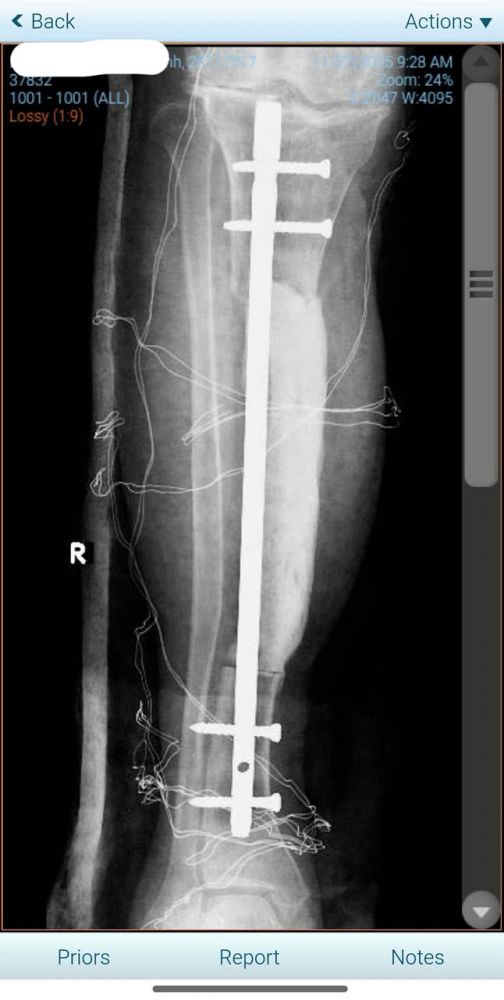

--Xử lý xương: Đóng đinh nội tủy để cố định trục chi, kết hợp đắp Cement spacer (xi-măng kháng sinh) vào phần khuyết xương để giữ trục và ngăn ngừa nhiễm trùng.

Hình 5: Phần xương chày còn lại được giữ trục bằng đinh nội tủy